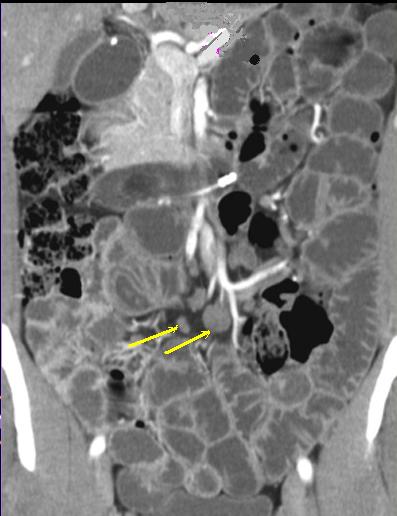

Signe de peigne le long du

ileon se voyait si net . C'est le signe de

hyper- vascularise mesenterique tres

particulairement dans maladie de Crohn . |

" Comb sign " peut voyait en

particulairement tres net . Image TDM de maladie de

Crohn en coupe coronale . |